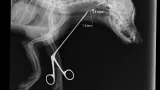

Maleni pas mješanac pogođen je dijabolom u vrat, a budući da je metak ostao smješten na nezgodnom mjestu blizu kralježnice, veterinar Mate Karaula iz Daruvara koji liječi Lenu, odustao je od vađenja metka zbog daljnjeg rizika po kujicu.

Prema nalazu veterinara dr. Mate Karaule, rendgenska snimka pokazala je da se metak, točnije dijabola, nalazi u području između atlasa i aksisa – dijela vratne kralježnice.

- Veličina projektila procijenjena je na 6,10 do 5,16 milimetara, a zbog dubine položaja i blizine kralježnice procijenjeno je da bi pokušaj vađenja mogao izazvati ozbiljne komplikacije. Zbog toga se odustalo od kirurškog vađenja metka.

Pas je primio injekcijsku sedaciju, obavljene su dvije rendgenske snimke i kirurška obrada rane, kazao nam je dr. Karaula.